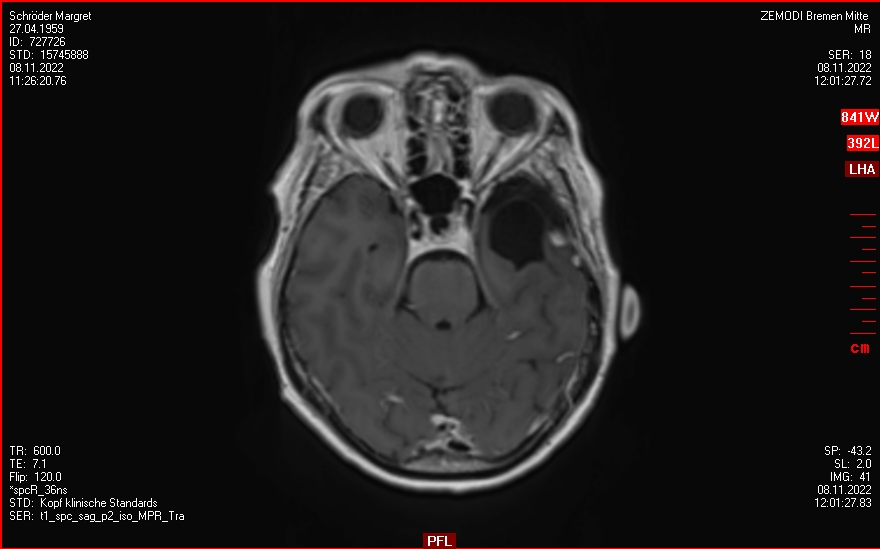

2019-2020

Ein Rezidiv wächst langsam

Die Tumorkonferenz vom Krankenhaus Bremen-Mitte rät zum Abwarten.

Der beratende Arzt dort, findet eine Bestrahlung im Gamma-Knife nicht falsch.